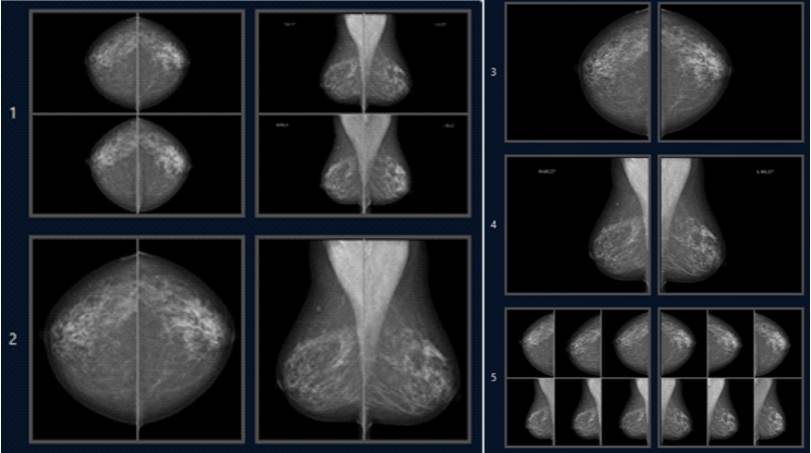

Figur 4. Exempel på ett visningsprotokoll för screeningbilder.

Kap12_Fig4.jpgBilderna presenteras i fem olika visningar. I den första visningen presenteras de aktuella bilderna överst, och jämförande bilder från näst föregående screeningomgång under dem. Därefter följer visningar av de aktuella screeningbilderna i olika storlek. I den avslutande visningen presenteras de aktuella bilderna i mitten av skärmen, omgivna av bilder från de två närmast föregående screeningomgångarna.